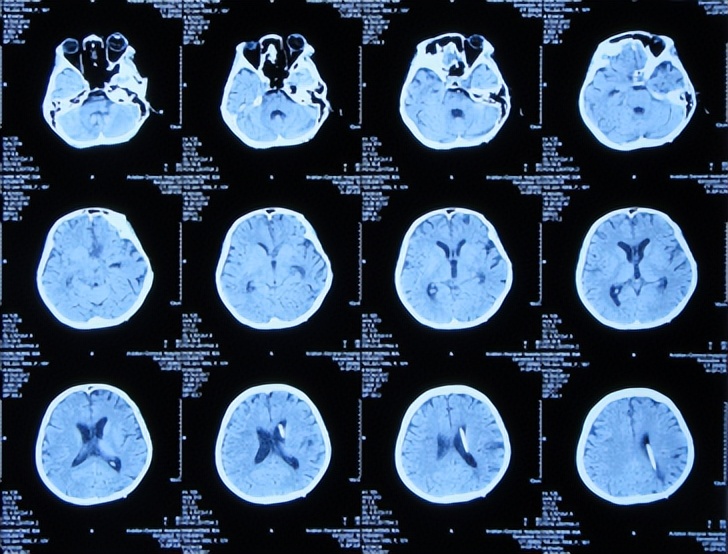

但发病后5天即2017年3月25日,从学校宿舍的上铺下来时因发热虚弱摔下,右眼眶外伤,就诊于第1家的陕西省西安某三甲医院,查脑CT( 图-1 )后认为右额颞部硬膜下有血肿,胸部X线检查未见异常(片子丢失)。

图-1: 2017年3月25日脑CT